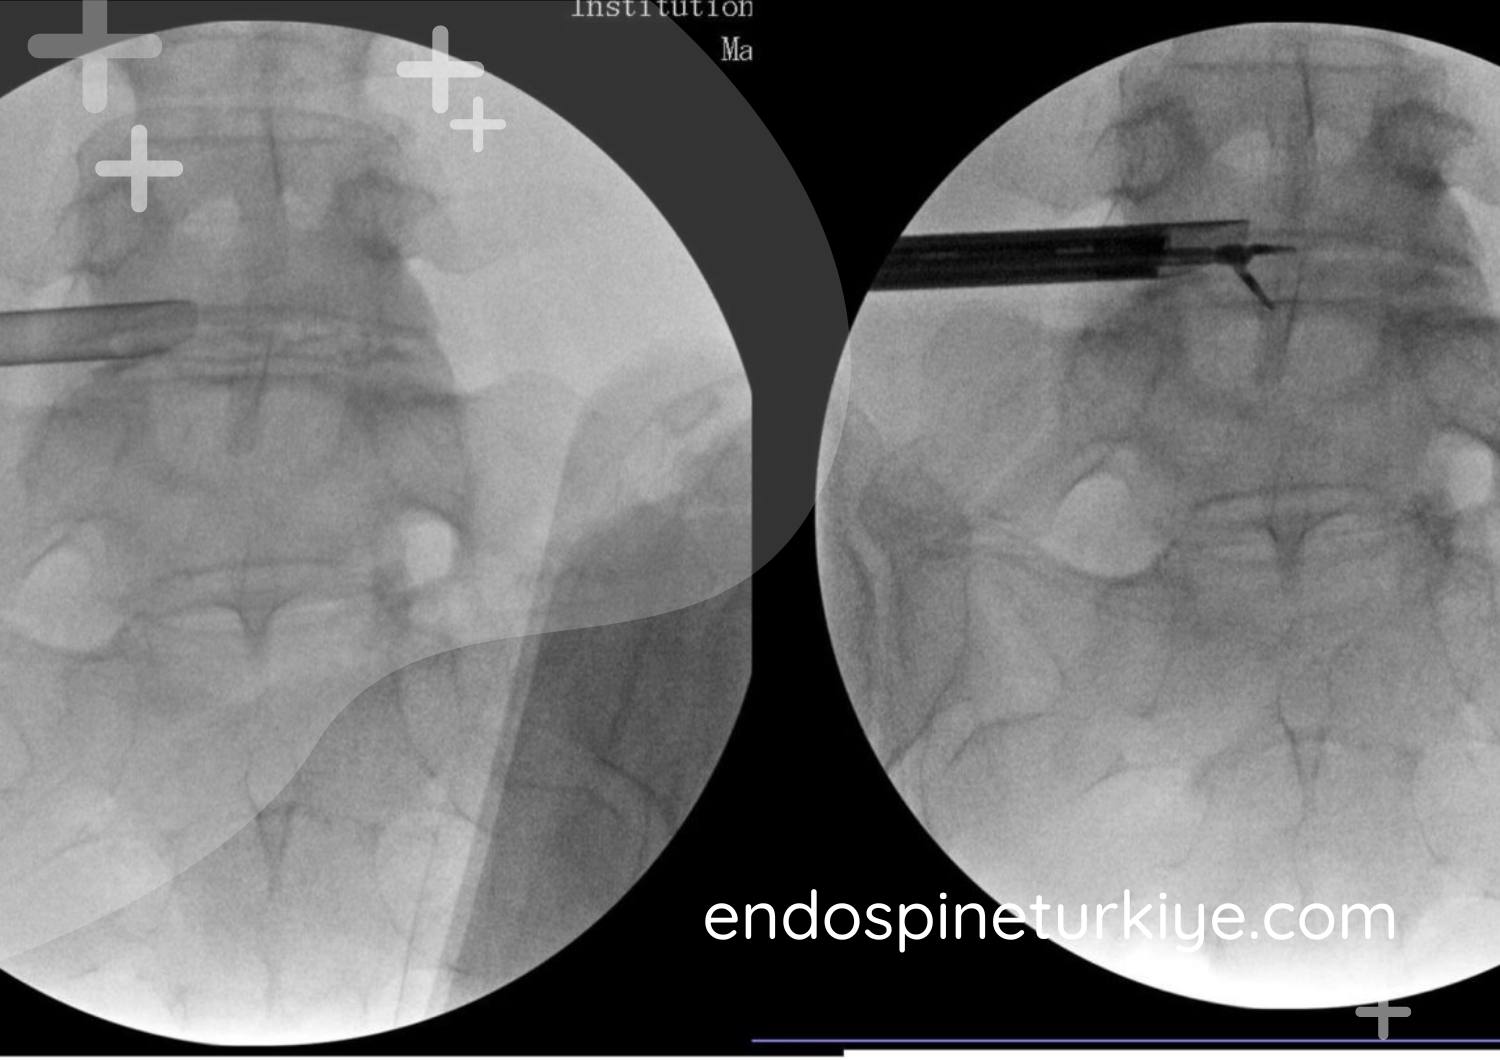

Kapalı Bel Fıtığı Ameliyatı Aşamaları

Ön Değerlendirme

MR tetkiki, kapsamlı fizik muayene ve cerrahi stratejinin oluşturulması gerçekleştirilir.

Endoskopik Cerrahi

6mm'lik açıklıktan endoskop konumlandırılır, HD görüntüleme altında fıtık materyali uzaklaştırılır.